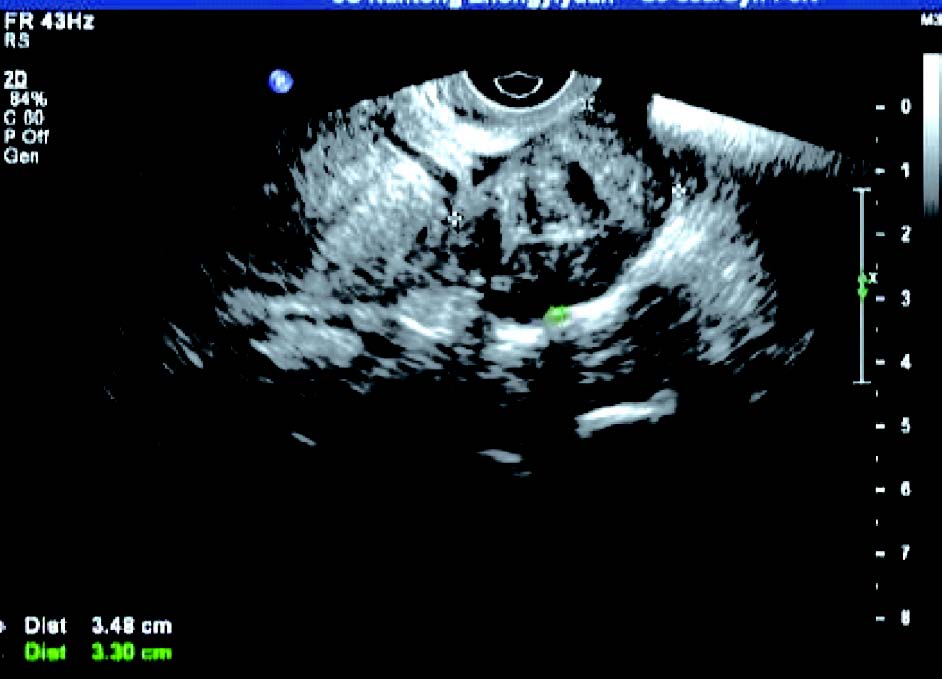

3. 黏膜下肌瘤

子宫内膜变形或缺损,内膜下肌层可见低回声结节突向宫腔,肌瘤完全突入宫腔时,宫腔内显示实性占位,但肌瘤与宫腔内膜间有裂隙,呈现“宫腔分离征”。CDFI 检测:瘤体周边呈环状或半环状血流信号,内部呈条状血流信号。